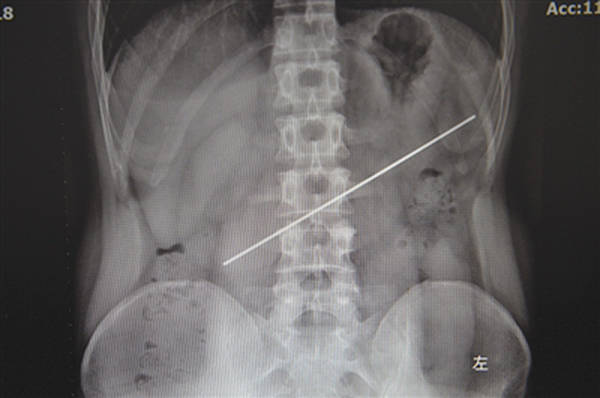

拍了X光片後,劉斌和同事發現,男子體內有一根長約20釐米的金屬異物。“當時很疑惑,那麼長,不太可能吞得進去;另外,這樣的金屬異物進胃後,不太可能一年沒有症狀。”劉斌解釋,鋼條很容易戳破胃壁造成胃穿孔,“胃裏的物質會流入腹腔,引發感染,嚴重者可致命。”

X光片顯示鋼條在患者體內 本文圖均為成都商報